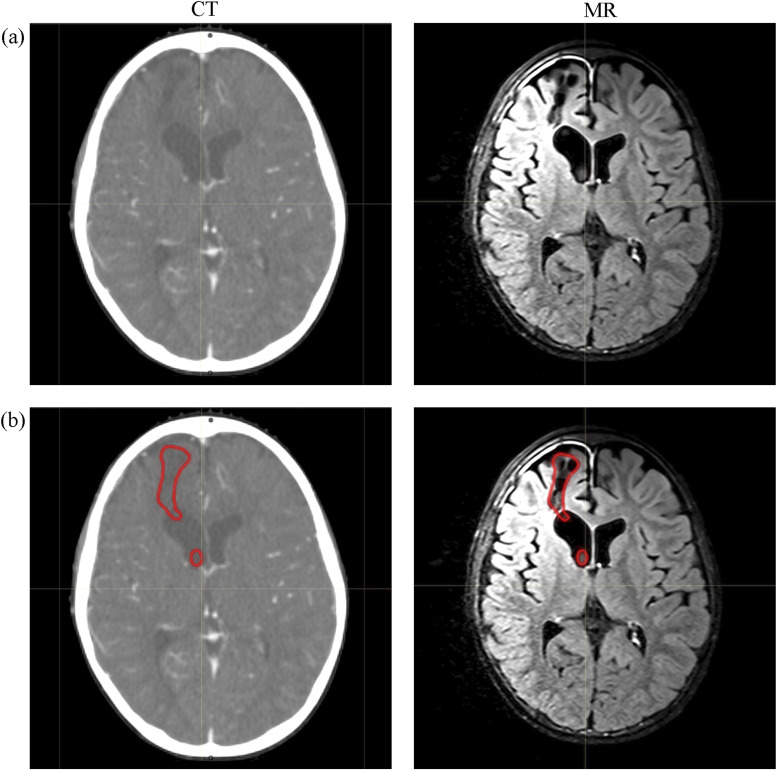

背景和目的:人工智能(AI)是一种试图像人类一样思考并模仿人类行为的技术。由于人类的参与是放射治疗(RT)中主要的不确定性来源,因此人工智能被认为是放射治疗(RT)中许多依赖人类的步骤的替代方案。这项工作的目的是对目前有关人工智能在放射治疗中应用的文献进行系统总结,并从临床角度阐明人工智能在放射治疗实践中的作用:对 PubMed 和 Google Scholar 进行了系统的文献检索,以确定从开始到 2022 年涉及 RT 中人工智能应用的原始文章。如果研究报告了原始数据并探讨了人工智能在 RT 中的临床应用,则被纳入研究:所选研究分为 RT 的三个方面:器官和病灶分割、治疗计划和质量保证。针对每个方面,本综述讨论了这些人工智能工具如何参与到 RT 方案中:我们的研究表明,在复杂的 RT 过程中,人工智能是依赖人力的步骤的潜在替代方案。

Results: The selected studies were categorized into three aspects of RT: organ and lesion segmentation, treatment planning and quality assurance. For each aspect, this review discussed how these AI tools could be involved in the RT protocol.